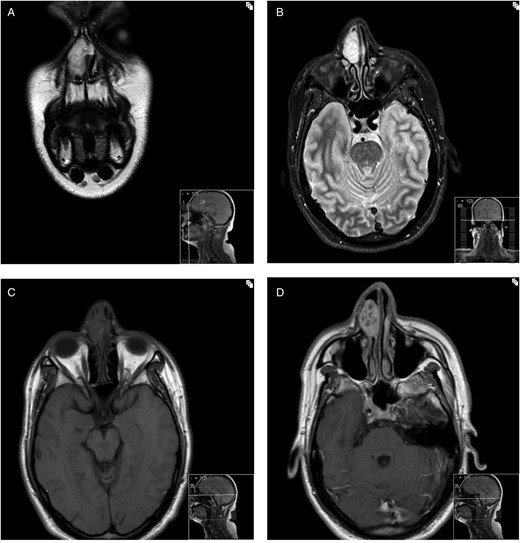

Non-contrast CT assessment of the sinonasal region was performed which revealed a soft tissue lesion arising from the right side of the nasal septum (Fig. 1). At the initial discussion at the local head and neck multidisciplinary team meeting, radiological opinion was that the lesion may possibly represent olfactory neuroblastoma, inverted papilloma or pleomorphic adenoma of the septum and that MRI would be beneficial in diagnosis. MRI imaging of the lesion showed general increased T2 signal but with heterogeneous nodular T2 heterogeneity (Fig. 2a and b). On the unenhanced axial T1-weighted sequence a small focus of T1 shortening was noted in keeping with some low volume focal cystic degeneration within the tumour (Fig. 2c).

(A) Coronal image of T2-weighted turbo spin echo (TSE) MRI of the sinonasal region. (B) Axial image of STIR (short tau inversion recovery) MR sequence through the sinonasal region. (C) Axial image of T1-weighted MR sequence through the sinonasal regions. (D) Post-contrast T1-weighted axial image through the sinonasal region.

The MRI findings in the previous cases reported in the literature have shown specific appearances including the ‘target sign’ which this lesion did not exhibit and the ‘fascicular sign’ which this lesion did exhibit on the T2-weighted sequence [1, 7, 8]. The presence of these appearances may raise the possibility of a nerve sheath tumour [8].